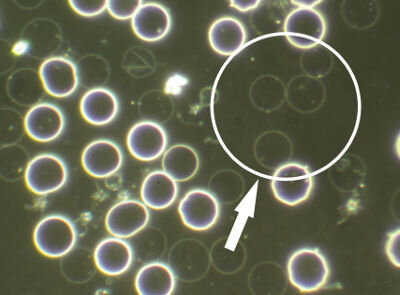

Considering how important to health our red blood cells are, it is vital that they are able to withstand the pressures they are under during circulation in order for them to deliver the essential-to-life oxygen to all our cells, tissues and organs.

If clients are consuming high levels of refined and processed fats, eating a diet of predominantly polyunsaturated fats and have little to no animal fats in their diet - it will show up in the blood in various ways:

• If the membranes are not formed properly – the red blood cells will lose their integrity in circulation.

• The rbc membranes will also oxidise easily creating red blood cells that are unable to carry out their functions.

• If the rbc membrane is deformed due to lack of appropriate fats they break under circulatory pressure. (picture of acanthocytes)

Yes! Healthy fats are essential for healthy cell membranes, especially red blood cells, and unhealthy fats can create unhealthy cell membranes which, if not corrected, can be responsible for many health issues:

You can use Live & Dry Blood Analysis to check the levels of oxidative stress and lipid peroxidation of your red blood cell membranes